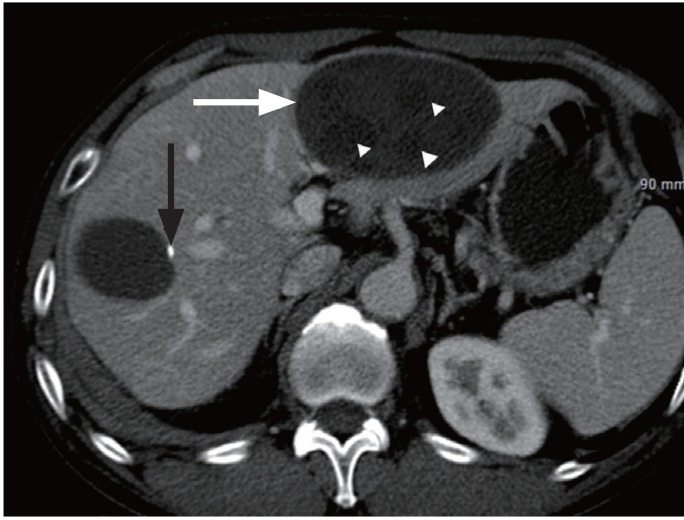

Figure 1

Contrast-enhanced abdominal computed tomography scan shows a smooth-margined large cyst in left lateral hepatic segment (white arrow), containing several small daughter cysts (arrowheads) and another cyst in the right hepatic lobe, with a small calcification along the wall (black arrow).